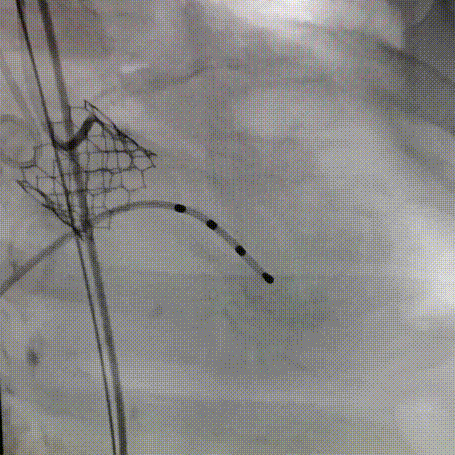

经左股动脉穿刺,置入6F股动脉穿刺鞘,将猪尾巴导管引导至腹主动脉,行主动脉造影。

180bpm下置入23mm球囊扩张,沿导丝入26mm 爱德华经导管人工瓣膜输送系统,仔细定位,180bpm下释放瓣膜。释放后血压低,起搏心率,复查主动脉根部造影,轻度反流,LCX可疑血流不好,沿导丝入EBU3.25到位,造影冠脉血流通畅,复查术中食道心超,人工瓣膜位置满意,开放良好,压差3mmHg,轻度反流。手术圆满结束。

术前造影

球囊预扩

过弓跨瓣

释放瓣膜

术后主动脉造影

左冠造影